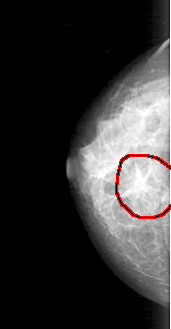

FILE: D_4185_1.RIGHT_CC.OVERLAY

TOTAL_ABNORMALITIES 1

ABNORMALITY 1

LESION_TYPE MASS SHAPE IRREGULAR MARGINS SPICULATED

ASSESSMENT 5

SUBTLETY 4

PATHOLOGY MALIGNANT

TOTAL_OUTLINES 1

BOUNDARY

RIGHT_CC LINES 3946 PIXELS_PER_LINE 2041 BITS_PER_PIXEL 12 RESOLUTION 43.5 OVERLAY